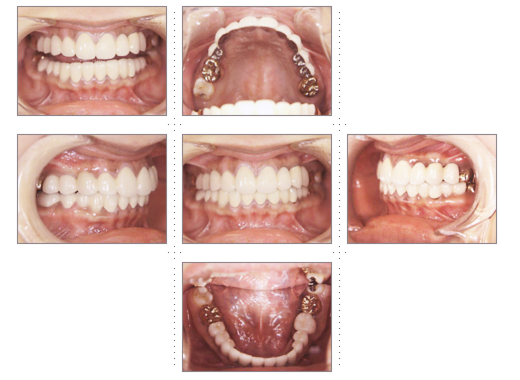

症例1

理学療法士 36才 女性

上下の歯並びを直したいというご希望で、来院。

術前と術後では、歯並び表情が変わった事はもちろんのこと、顔の形も変わり、「美容整形をしたように小顔になれました」と喜んでいただけました。